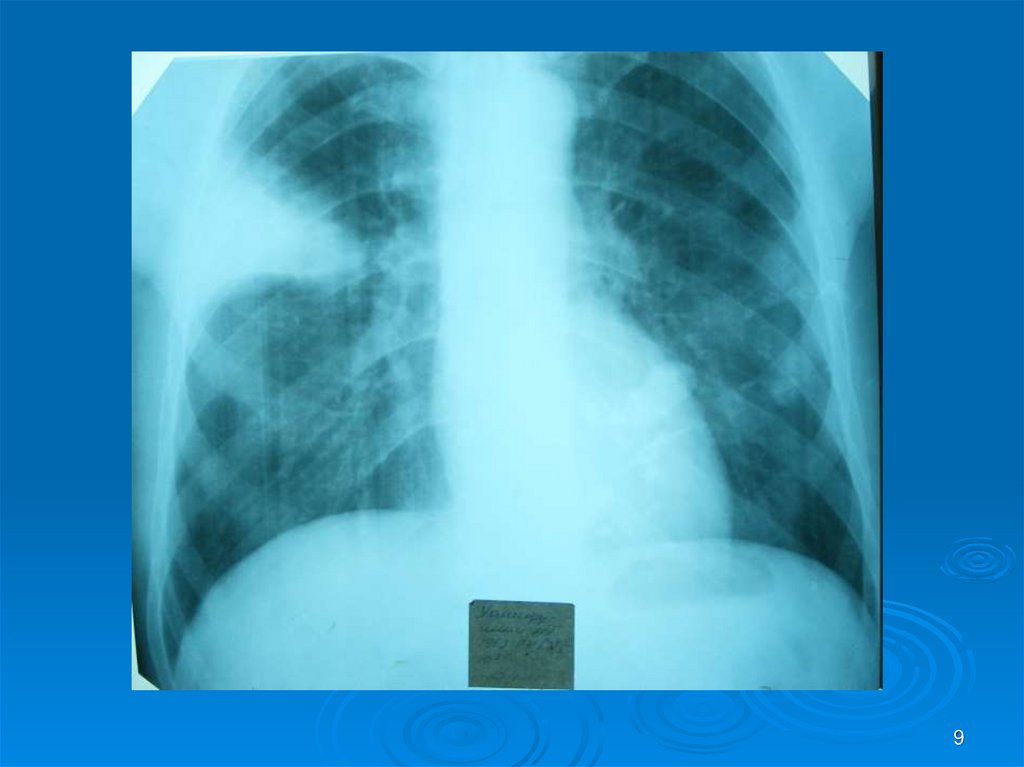

9.

9